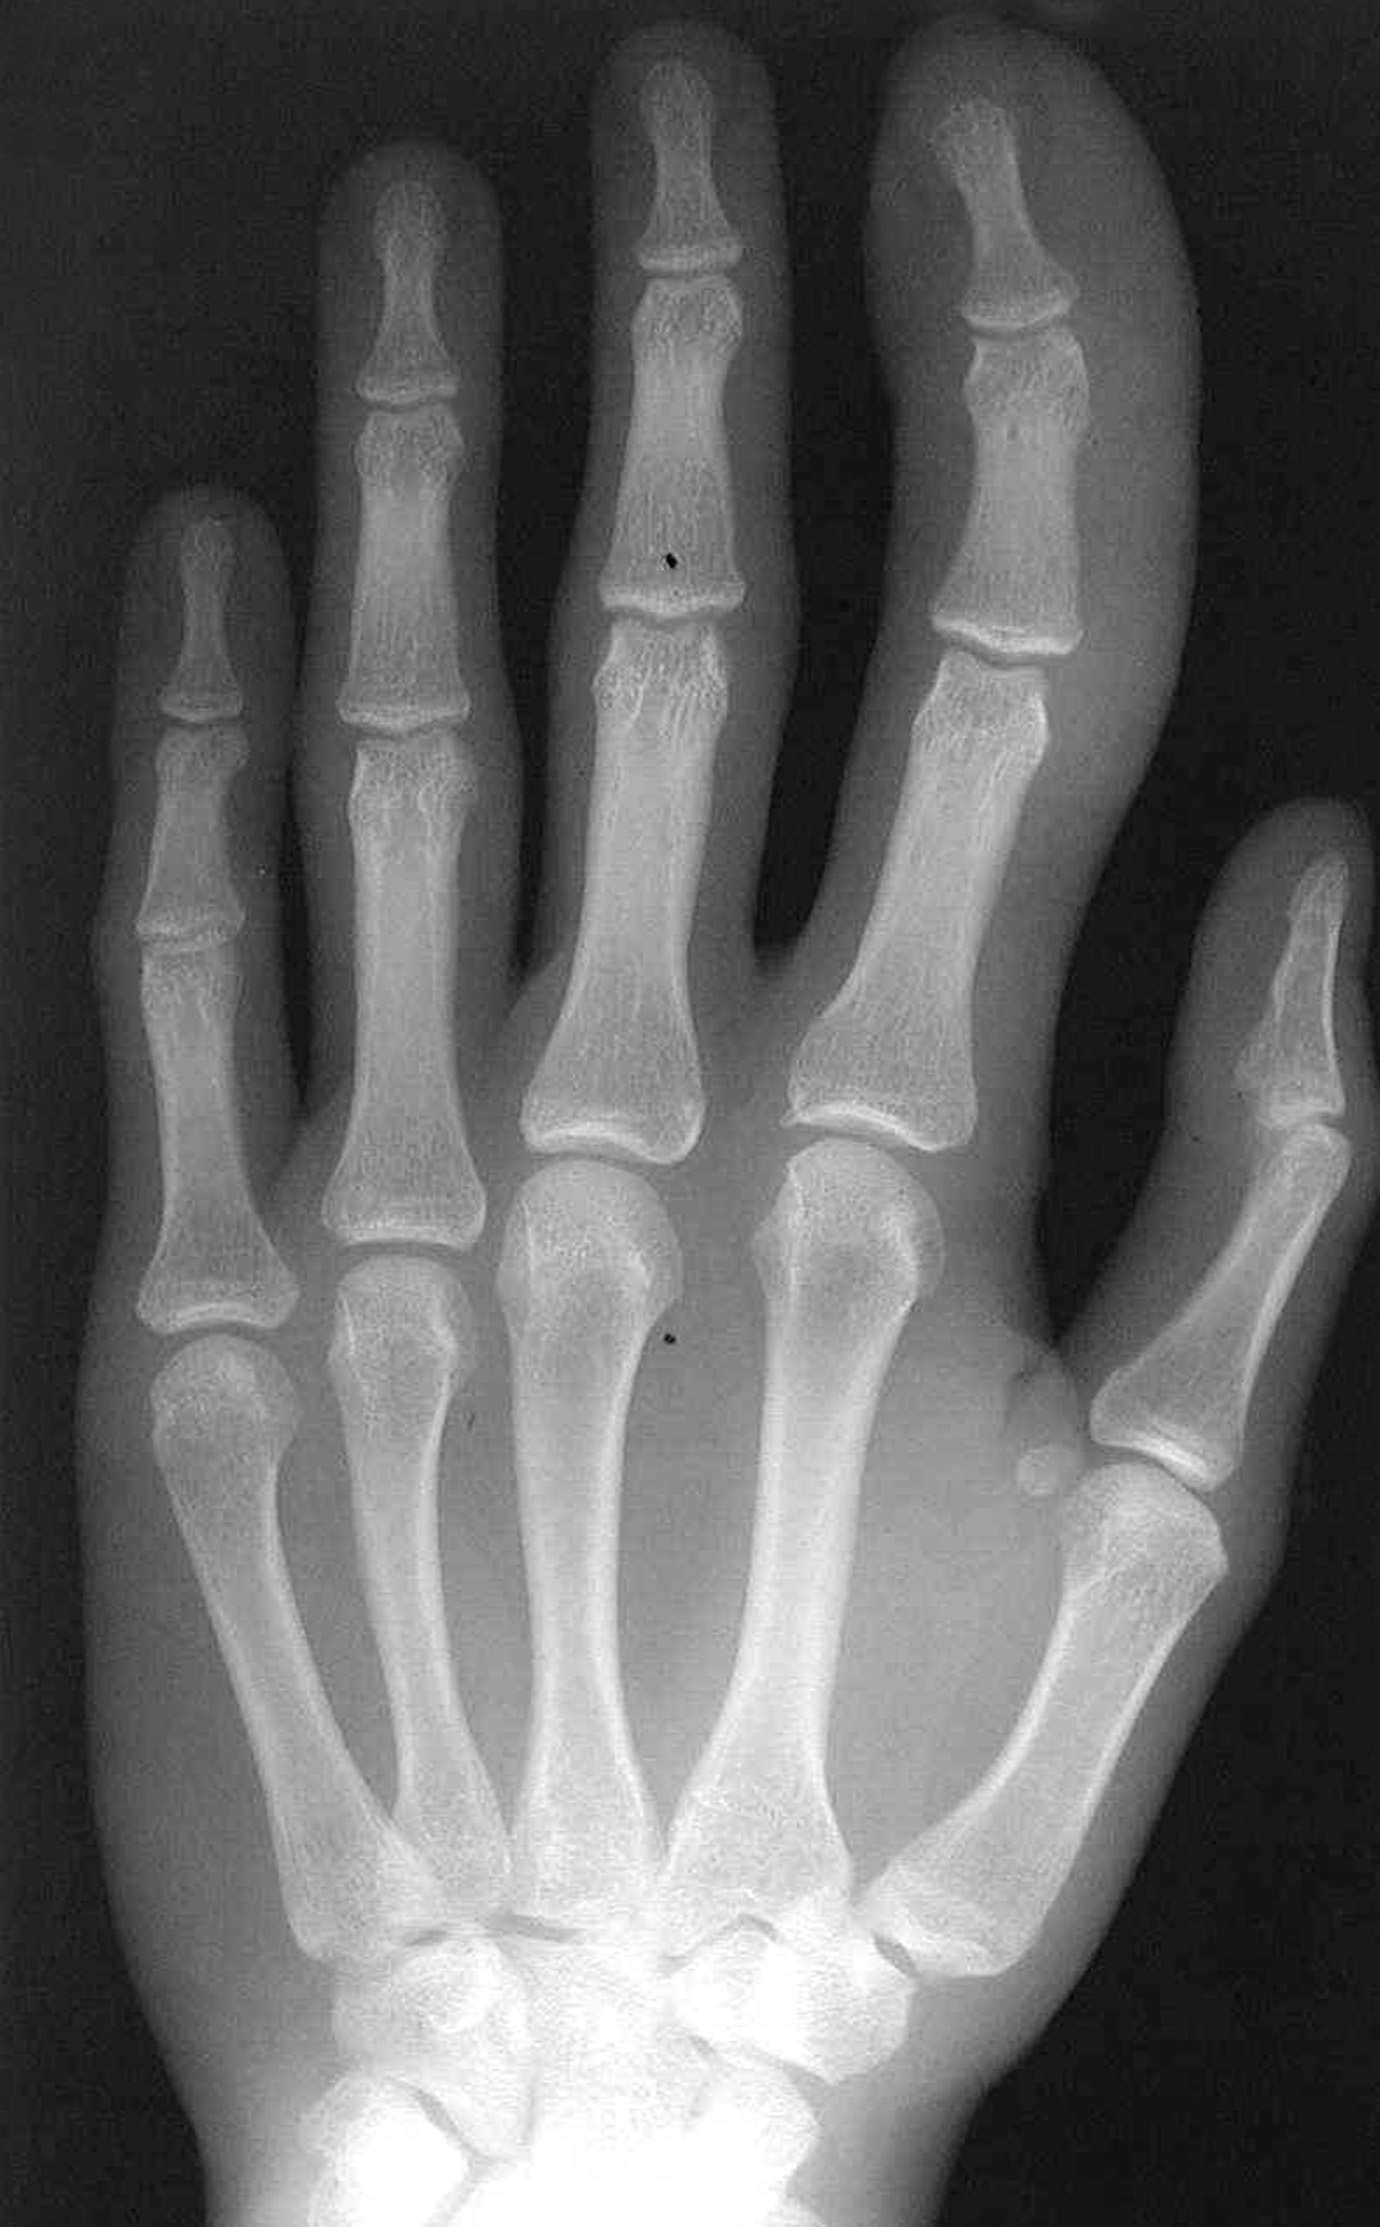

The patient reports no abnormal sensations in the enlarged finger. Significant fatty tissue is present, but there are no discrete masses. He has no pain on palpation or neurologic defect, and the finger has a full range of motion. Oblique and posteroanterior radiographs of the hand are shown.

The radiographs demonstrate prominent soft tissue and bone overgrowth in the finger, consistent with the clinical and radiographic diagnosis of megadactyly. The soft tissue overgrowth is most marked at the distal end of the digit and the volar aspect. The intermetacarpal space is also enlarged. The finger has a slight lateral curve at the apex but no underlying bone deformity. Several lucent areas represent fat. Macrodystrophia lipomatosa was the subsequent diagnosis.